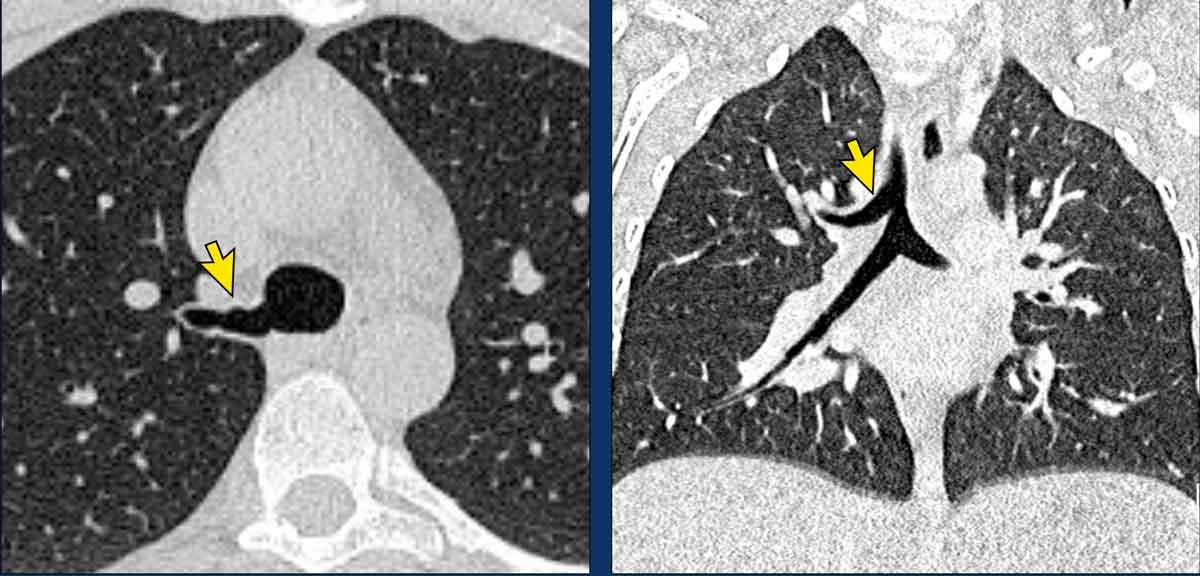

Hình ảnh

Teo phế quản ở thùy dưới phổi trái ở nữ giới 47 tuổi.

Cấu trúc phân nhánh điển hình với nhu mô phổi sáng xung quanh, đại diện cho phế quản giãn rộng chứa đầy chất nhầy (mũi tên).

Không có lỗ vào của phế quản phân thùy đáy sau (LB10) và ứ khí lan rộng của nhu mô phổi liên quan, thấy rõ nhất trên các tái tạo phổi.

Hình ảnh MIP (chiếu cường độ tối đa) lát dày cho thấy các đường thở giãn rộng chứa đầy chất nhầy ở thùy dưới phổi trái (mũi tên).